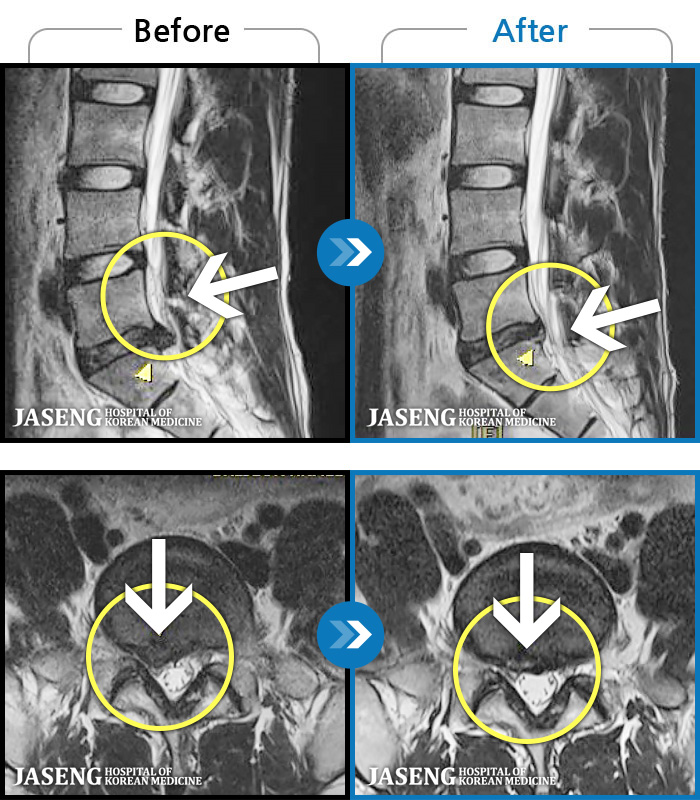

허리디스크

광주 · 김동은 원장

허리 통증과 양측 둔부부터 허벅지, 발목 부위 저리는 증상으로 내원하셨습니다.

촬영시기

2025.05.09 ~ 2025.12.18

2025.12.22